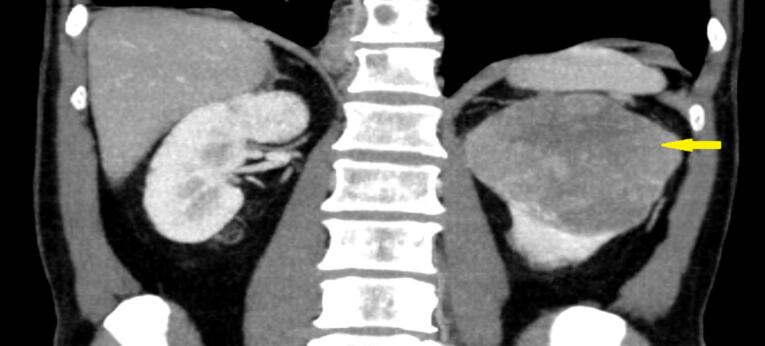

Chromophobe renal cell carcinoma (ChRCC) is a rare subtype of renal cell carcinoma (RCC). We present a case of a 61-year-old male with ChRCC who exhibited unusual metastasis to the retro-orbital area, a site rarely affected by RCC. The patient experienced diplopia and proptosis, prompting treatment with sunitinib and palliative radiotherapy. Remarkably, rapid improvement in ocular symptoms was observed following radiotherapy. Despite this localized response, the patient's overall condition deteriorated, highlighting the aggressive nature of ChRCC. This case underscores the importance of considering ChRCC in metastatic presentations and the potential efficacy of local palliative interventions.